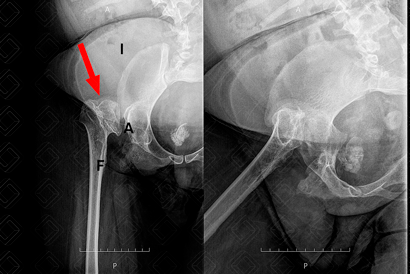

Texto alternativo para a imagem Legenda: A = acetábulo; F = fêmur; I = ilíaco.

Descrição da figura: Radiografia do quadril direito estudo em AP e Lowenstein. Observa-se importante deslocamento superior e lateral da cabeça femoral direita que não articula mais com a cavidade acetabular (seta vermelha).